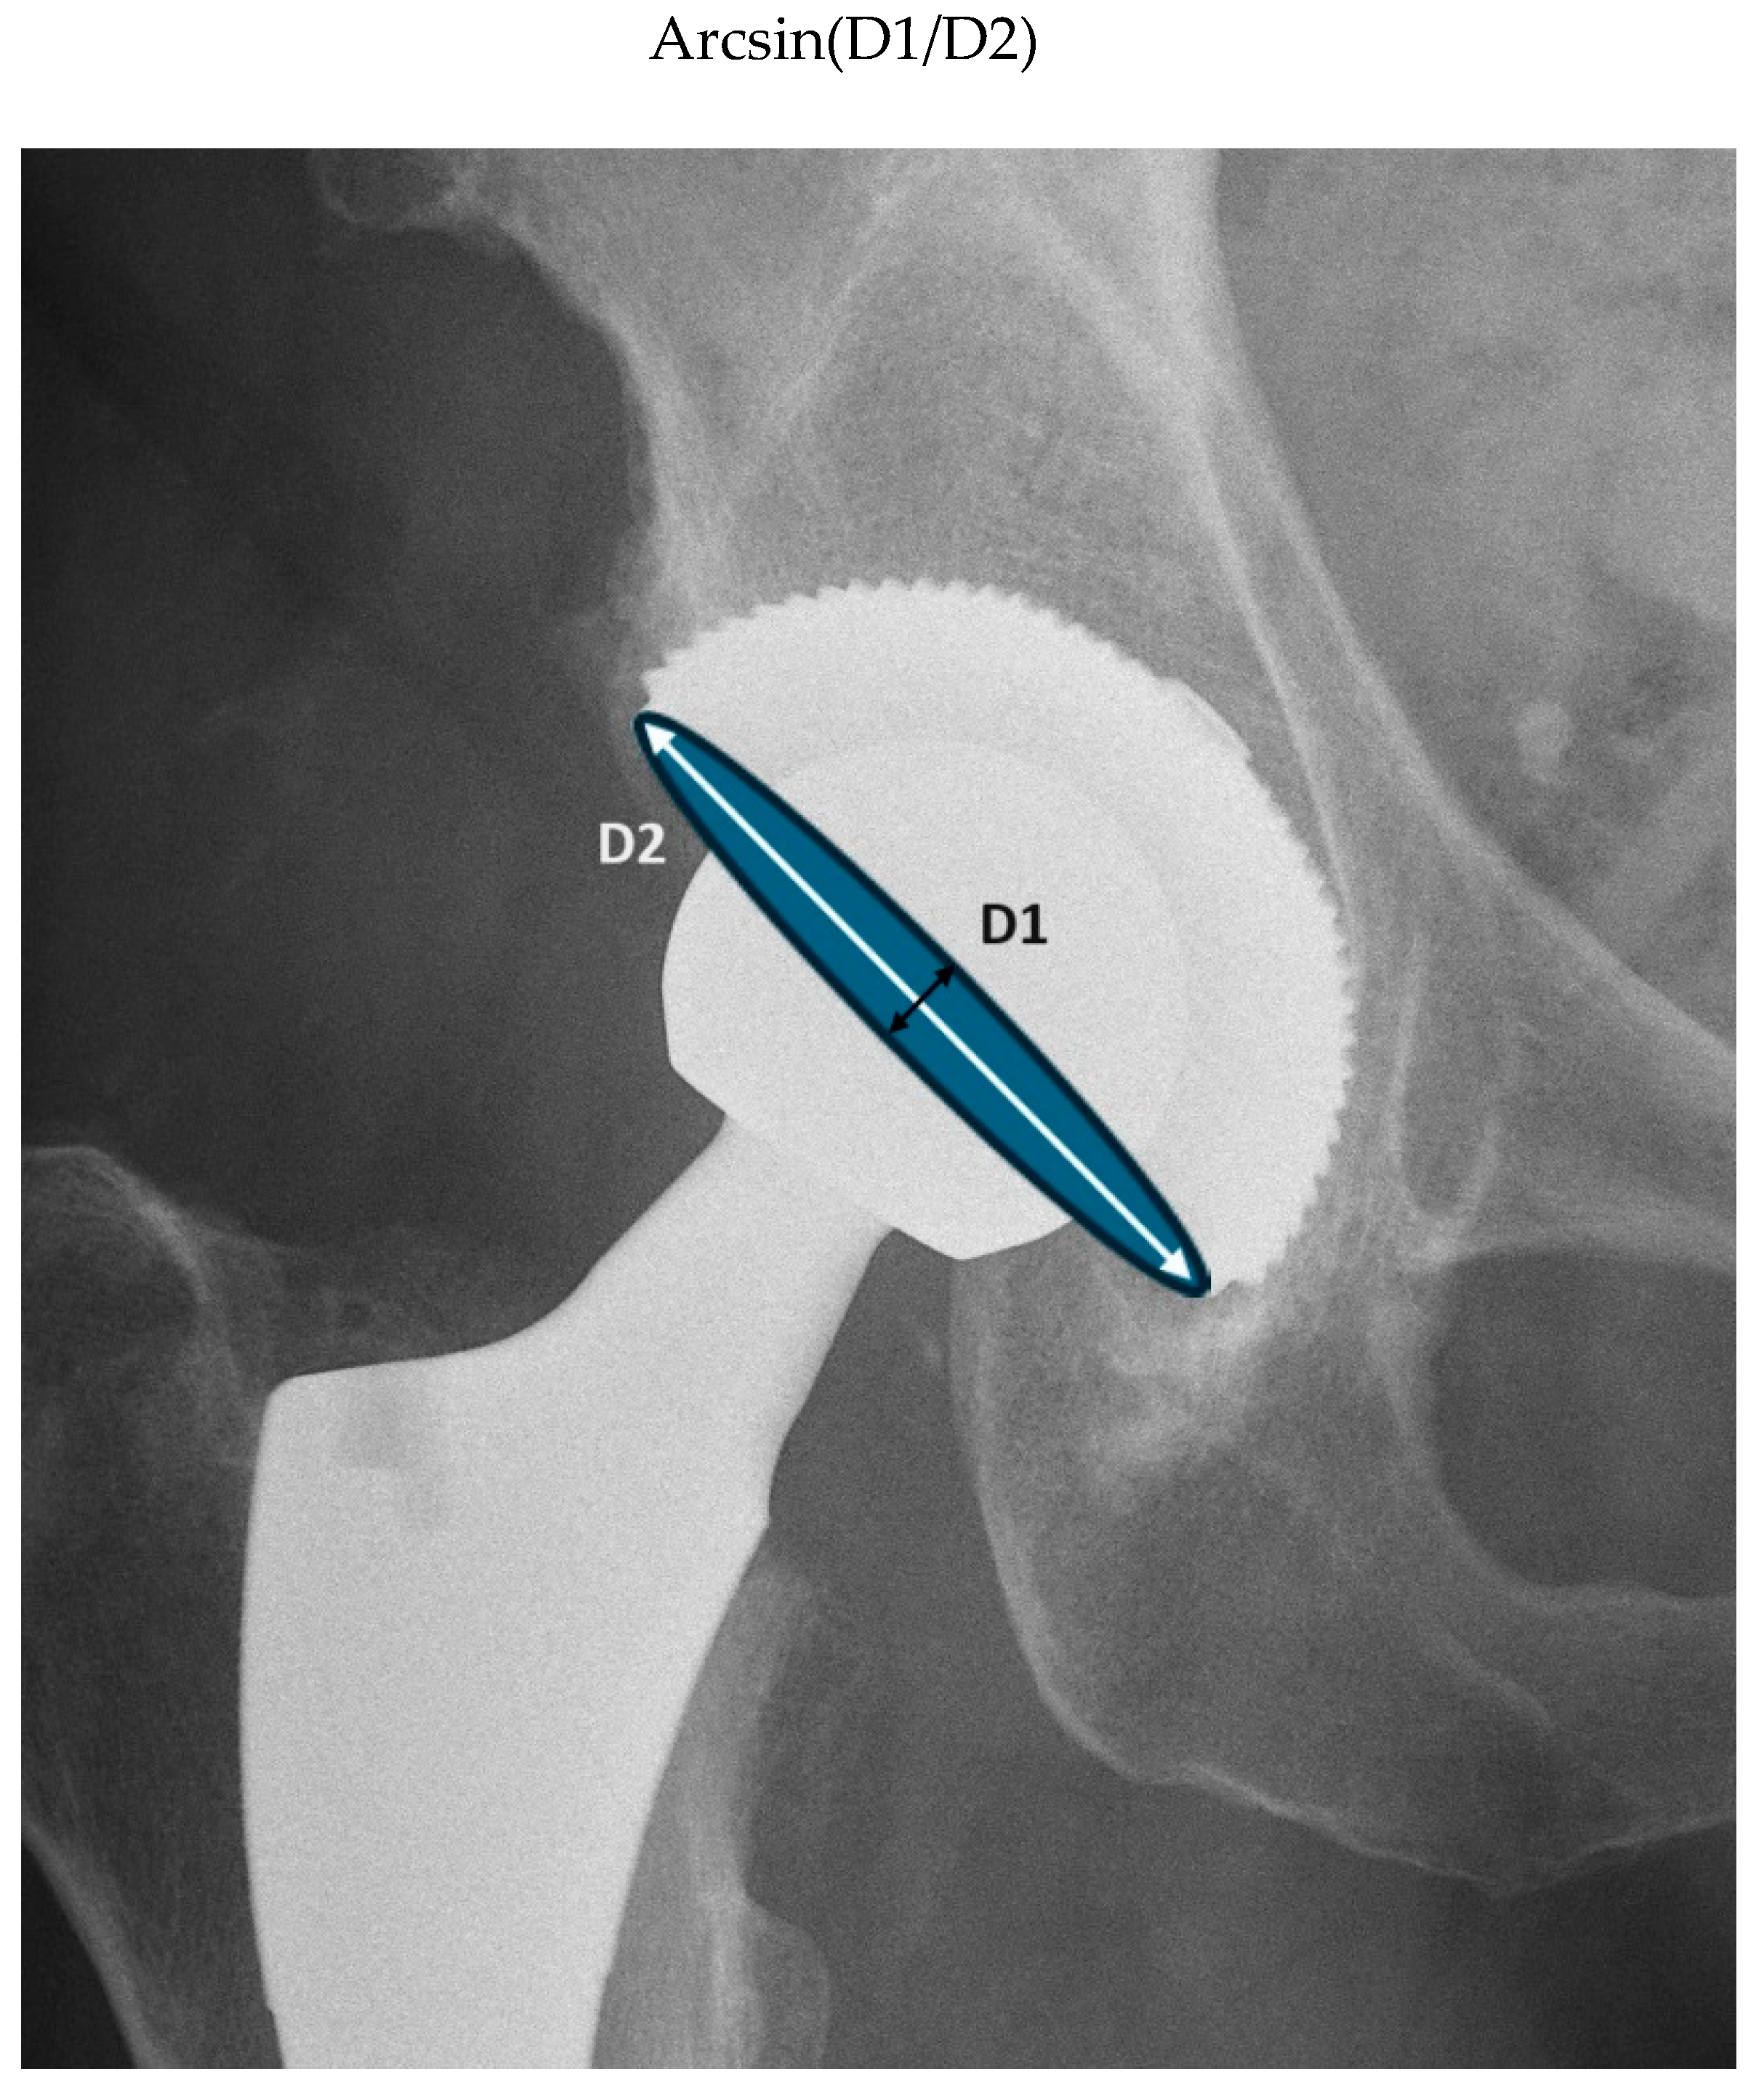

- Manjunath, K.S.; Soruban, V.; Gopalakrishna, K.G. Evaluation of radiological methods of assessing cup anteversion in total hip replacement. Eur. J. Orthop. Surg. Traumatol. Orthop. Traumatol. 2015, 25, 1285–1292. [Google Scholar] [CrossRef] [PubMed]